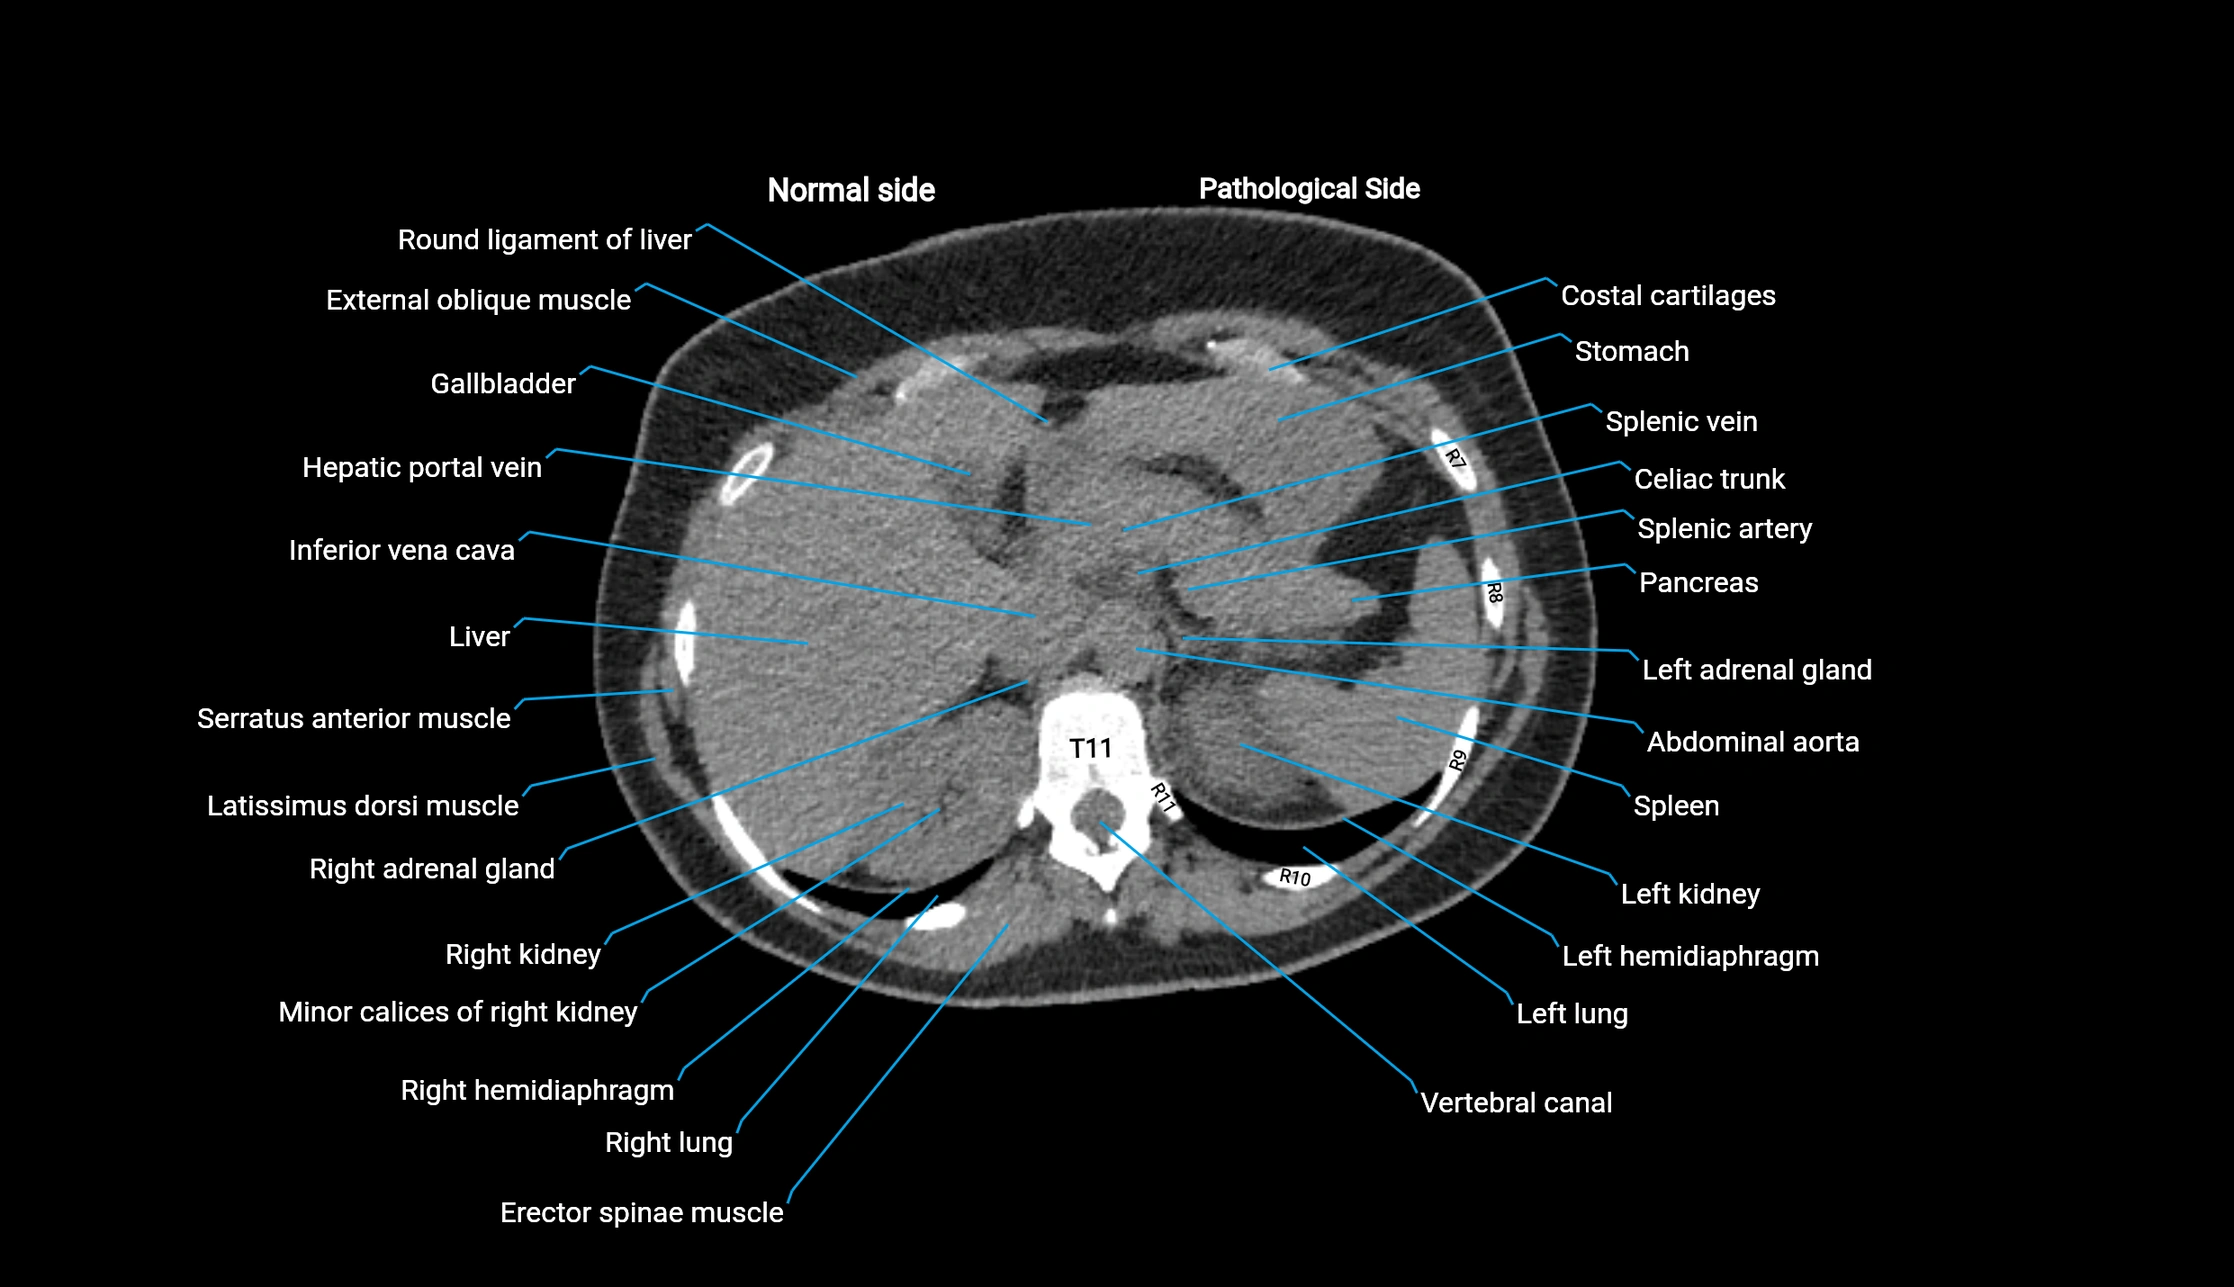

CT image

image